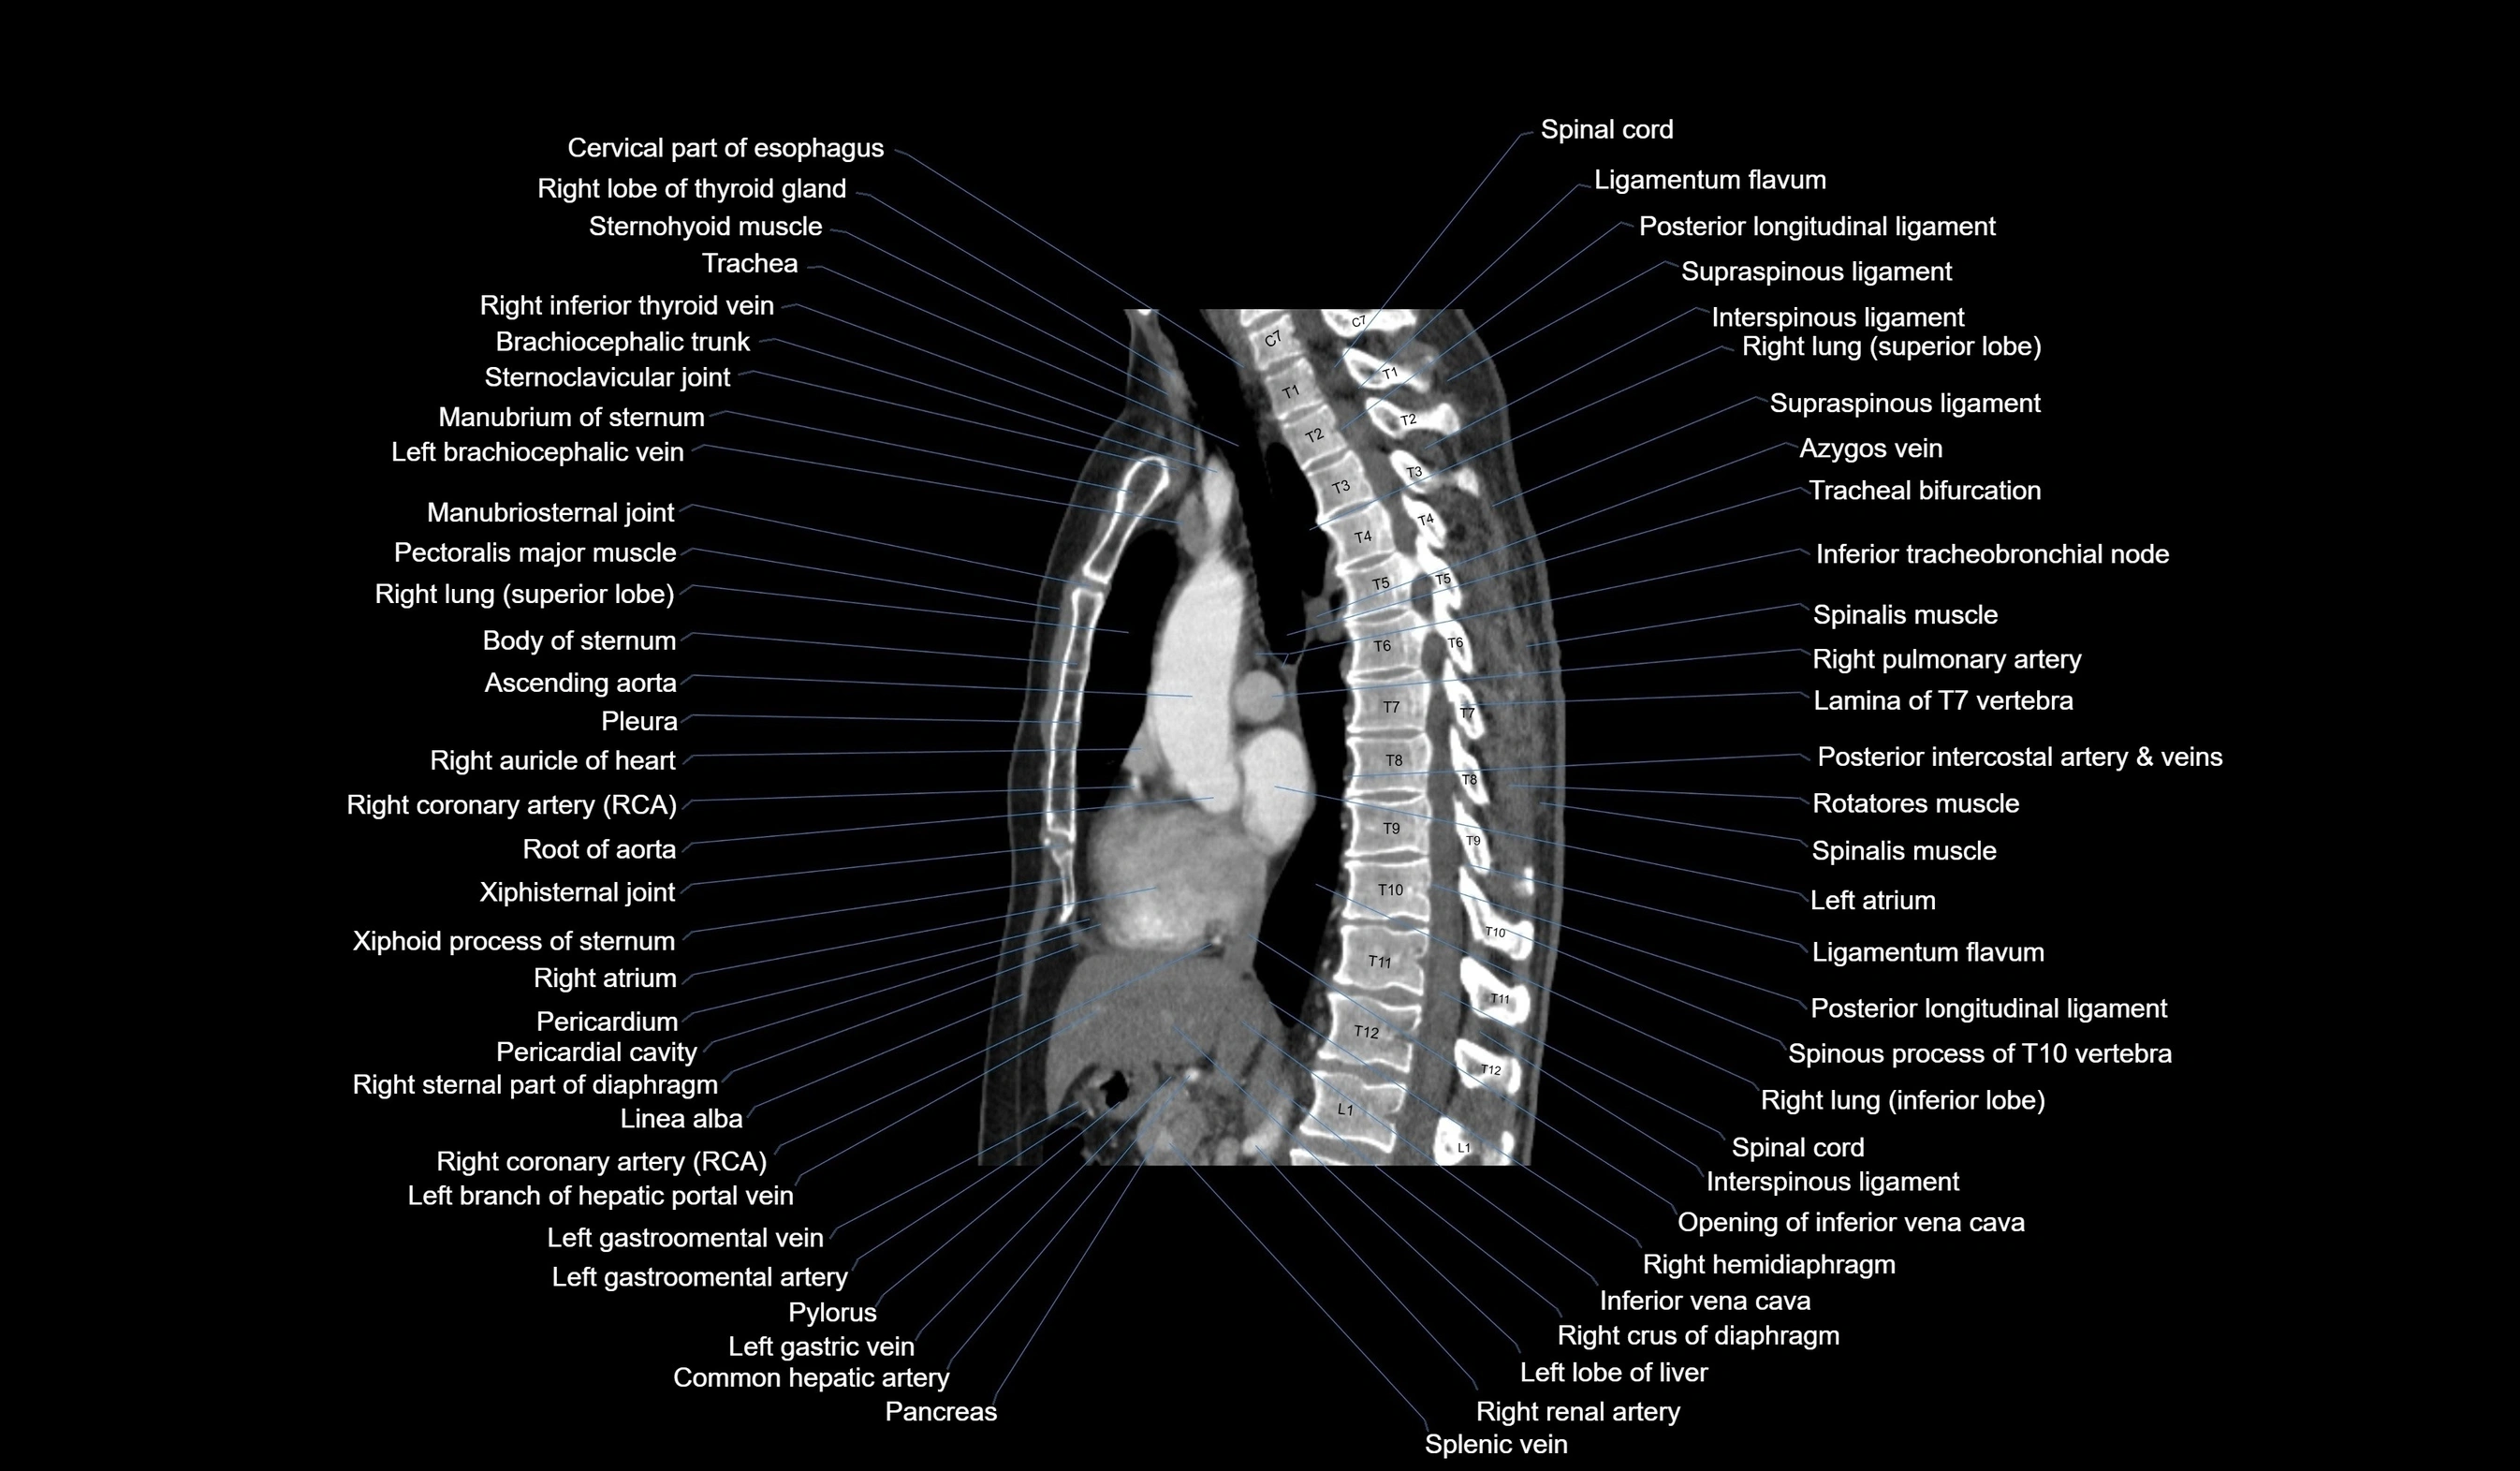

CT images